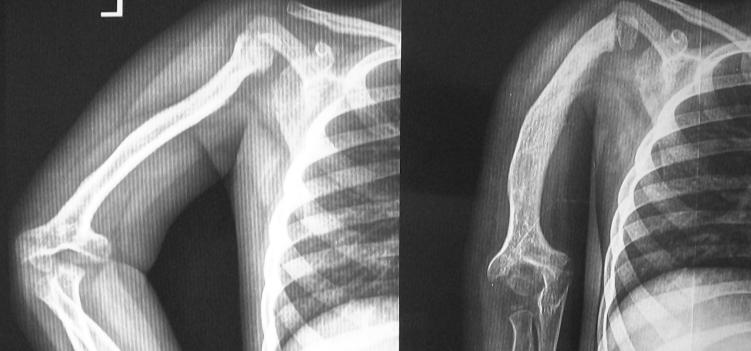

The shoulder was opened and thoroughly washed. Antibiotics were adequately given for 6-8 weeks and the infection was eradicated. However,

residual complications like deformity, subsequent pathological # and limb length discrepancy were seen during follow-up.

Limb-length

Limb-length Discrepancy ((LLD)! (right upper limb shorter)